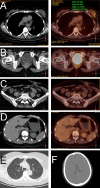

Methods: We present a case that till now is the first reported breast metastasis from rectal cancer pathologically diagnosed as a signet-ring cell carcinoma, and we review the current literature on this rare event. The detailed clinical data, histopathology, management, and follow-up aspects were gathered for analysis.

Results: A total of 15 cases were collected including the current case. Breast metastases from rectal cancer present at an average age of 47.7 years (range, 28 to 69 years) and appear with an average interval of 28.4 months (range, 5 months to 18 years) following primary tumor diagnoses. Of the 15 cases, 8 and 5 are pathologically diagnosed as adenocarcinomas and mucinous adenocarcinomas, respectively. Most cases (11/15) are accompanied by extramammary metastases. About half of the breast metastases (7/15) were to the left. In all cases, the main complaints were palpable mass. The average maximum diameter of the metastatic mass is 2.7 cm (range, 1-11 cm). The majority (8/12) of cases with accessible therapy information exclude the option of local surgery.

Conclusion: Previous cancer history and accurate immunohistochemistry data play critical roles to distinguish mammary metastasis from a primary neoplasm of the breast. Mastectomy and molecular-targeted drugs should be considered with priority if systemic condition supports them.